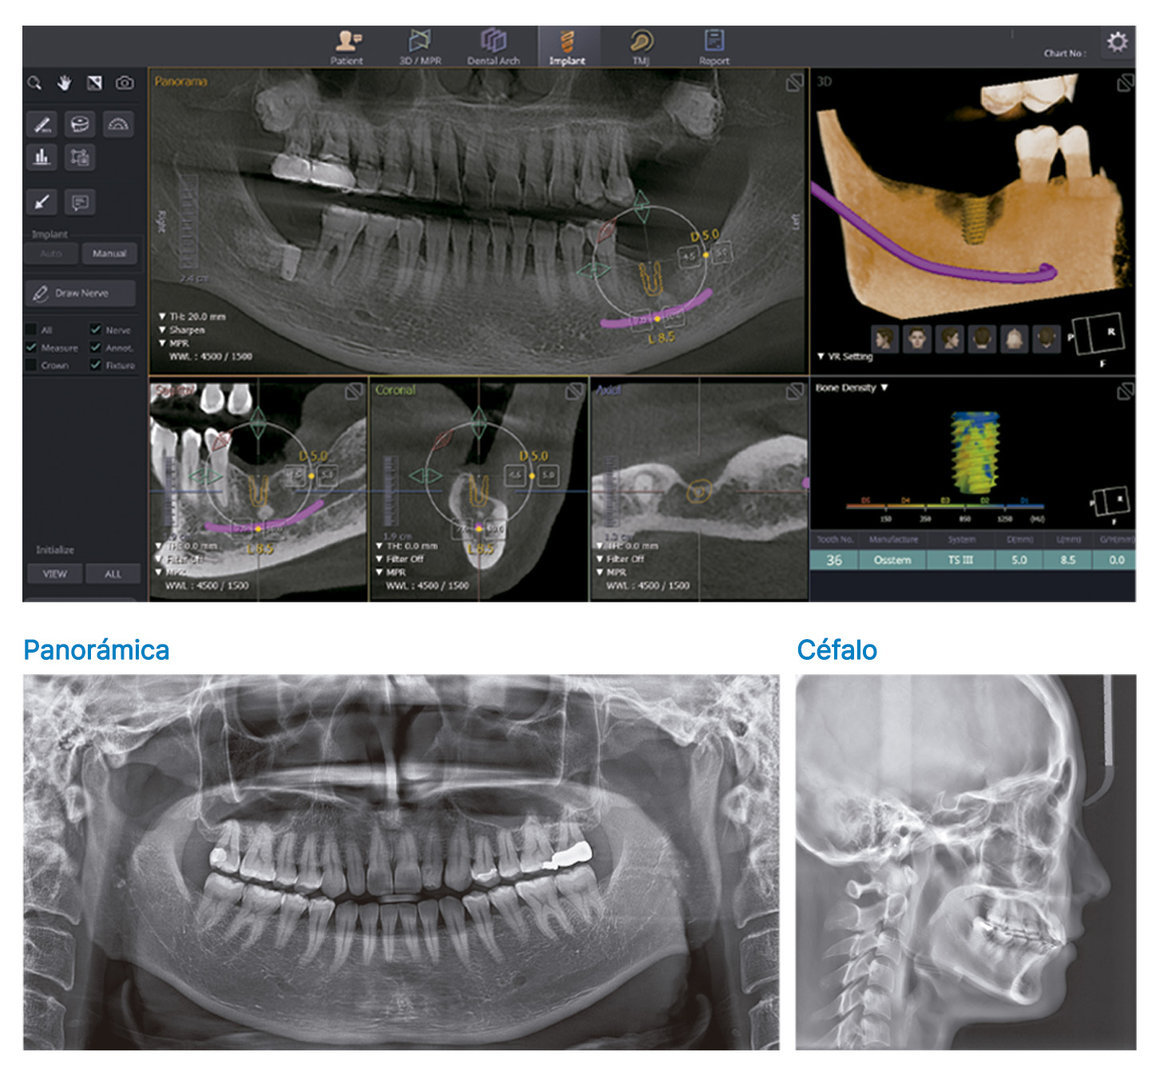

El T2 Plus es un sistema de imágenes fácil de usar que convierte las señales de rayos X en señales digitales para adquirir imágenes 2D y reconstruirlas en imágenes 3D, utilizando tecnología Pano, Céfalo y CT para el diagnóstico de estructuras anatómicas de áreas orales y maxilofaciales. Una de las características sobresalientes del T2 Plus es su sistema 3 en 1, que incorpora imágenes 3D, CT, Pano y Céfalo (opcional) en un solo sistema de imágenes. Esto lo convierte en una herramienta muy versátil que se puede utilizar para una variedad de diagnósticos, que incluyen ortodoncia, análisis de implantes y dientes impactados, análisis de arco completo y senos nasales e imágenes de ATM.

Modos de diagnóstico

Software